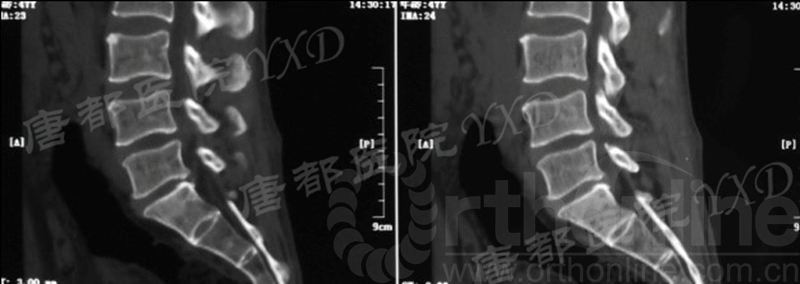

影像学检查:

诊断:腰椎椎间融合术后融合器后移

手术方案:显微镜辅助MI-TLIF腰椎翻修术